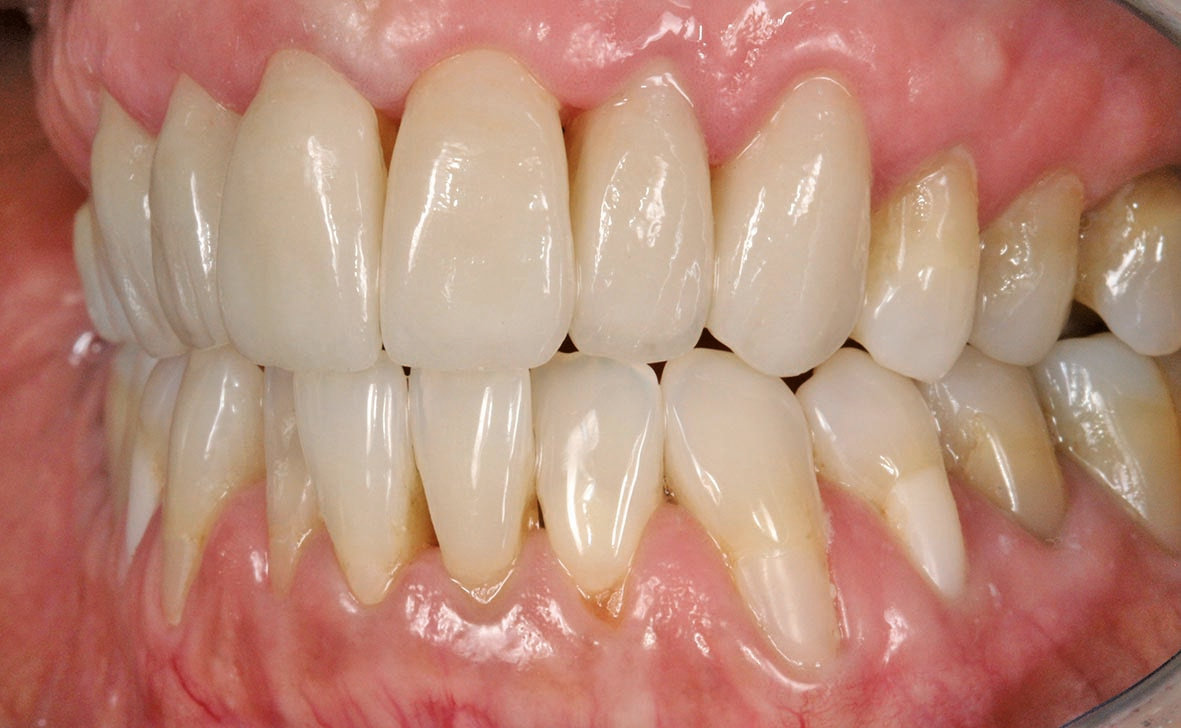

Die fertigen Veneers im Patientenmund

Wenn wir gerade von Alternativen sprechen: Im hier geschilderten Fall wäre ein Metallgerüst unterlegen gewesen, nicht nur wegen der Gefahr der Entblößung eines Metallrandes im Frontzahnbereich im Laufe der Zeit, sondern auch wegen der hohen Biokompatibilität von Zirkoniumdioxid: Die Wahrscheinlichkeit ist deutlich höher, dass sich die Gingiva wieder mehr an die Kronen anschmiegt. Hinzu kommt die geringe Plaqueanfälligkeit. Im Falle von Hera Zirkonia sehen wir darüber hinaus durch die niedrige Brenntemperatur bei Keramikbränden von nur 750 °C, dass die Farbstabilität des Gerüstmaterials ohne Chromaverlust erhalten bleibt. In Hinsicht auf die Ästhetik gefällt uns sehr, dass sich die Verblendkeramik beim Finish mechanisch gut auf Hochglanz polieren lässt.

Das Ergebnis hat nicht nur dem Behandler und der Patientin, sondern auch deren privatem Umfeld sehr gut gefallen. Dank der sorgfältigen Analyse, geschickter Materialwahl und eines tollen Behandlungskonzeptes konnten wir die Patientin sehr glücklich machen.